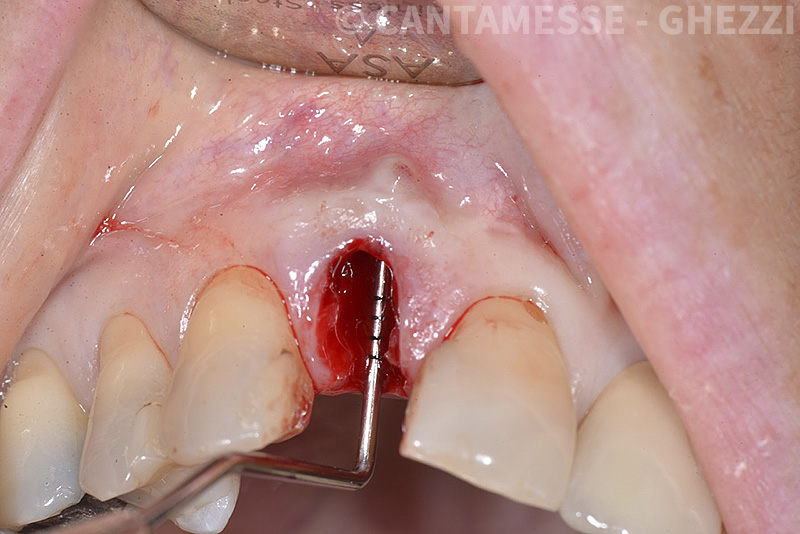

PREMESSA: in seguito all’estrazione dell’incisivo laterale superiore di destra, resasi necessaria per cause batteriche, si decide di affrontare il caso con il posizionamento di un impianto in sostituzione dell’elemento mancante dopo guarigione del sito infetto. Con tecniche rigenerative sia dei tessuti ossei mancanti a causa dell’infezione pregressa, sia dei tessuti gengivali che appaiono inizialmente troppo spostati in alto, si ripristina una corretta morfologia delle parabole (contorni) gengivali e delle papille interdentali (triangoli di gengiva tra due denti vicini).

Vengono utilizzati 2 tipi di provvisori: il primo, cementato ai denti vicini, viene utilizzato dal momento dell’estrazione del dente fino ad impianto osteointegrato (circa 6 mesi); il secondo, avvitato direttamente all’impianto, ha una funzione di prova estetica ma soprattutto di guida per la maturazione dei tessuti gengivali peri-implantari portandoli verso la maturazione completa prima di posizionare la corona finale in disilicato di litio.